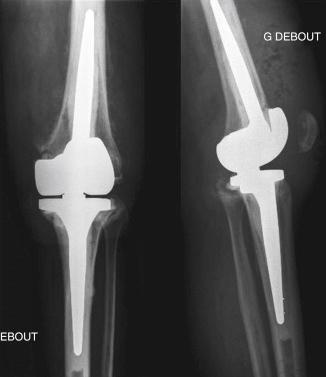

We performed a one-stage exchange with reconstruction using a hinged prosthesis with cemented stem extensions and provided immediate coverage with a gastrocnemius flap. Intraoperative samples confirmed the diagnosis. Postoperative antibiotic treatment was given intravenously for 2 weeks and orally for 3 months. The postoperative course was uneventful. After 2 years, the patient had only minor pain after strenuous activities. There were no signs of persistent infection, and no pathologic changes were observed on the final radiographs ( Fig. 35.2 ).

FIGURE 35.2, Case 1: Standard final radiographs. A, Anteroposterior view. B, Lateral view.